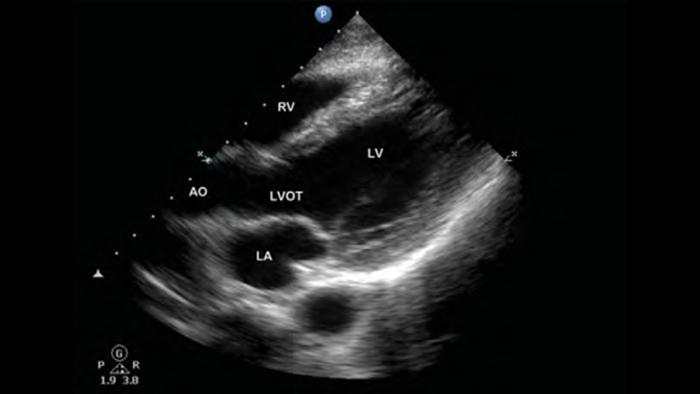

Use Lumify for airway and pulmonary assessment

Lumify POCUS solutions can help you detect the endotracheal tube within the trachea, assist in emergent cricothyrotomy procedures, diagnose pleural effusion and interstitial alveolar diseases.

Lumify S4-1 broadband phased array transducer

• 4 to 1 MHz extended operating frequency range

• 2D, color Doppler, M-mode, advanced XRES and multivariate harmonic imaging

• High-resolution imaging for abdominal and cardiac applications: Cardiac, OB/GYN, Lung, Abdomen and FAST imaging preset optimizations